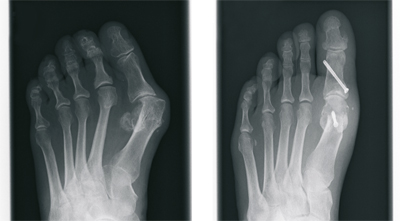

Beim Hallux valgus - im Sprachgebrauch häufig Ballenzehe genannt - handelt es sich um eine Abweichung der Großzehe nach außen, kleinzehenwärts. Diese Fehlstellung tritt häufiger bei Frauen auf. Die genaue Ursache ist nicht geklärt, sicherlich spielen falsches Schuhwerk und Erbanlagen eine große Rolle. Die unterschiedlichen Ausprägungen sind durch eine zunehmende Fehlstellung, verbunden mit Schmerzen, gekennzeichnet.

Von einer operativen Korrektur ohne Vorhandensein von Schmerzen, d. h. aus rein kosmetischer Sicht, ist abzuraten. Bei Auftreten von Schmerzen im Bereich der Großzehe ist die operative Vorgehensweise jedoch die einzig dauerhafte therapeutische Möglichkeit.

Nach ausführlicher Untersuchung, Betrachtung der individuellen Erfordernisse, sowie Analyse der Röntgenbilder wird die Behandlung festgelegt. Hierbei kommen verschiedene international anerkannte Operationsverfahren zur Anwendung. Wir verwenden dabei modernste Platten und Schrauben aus Titan.